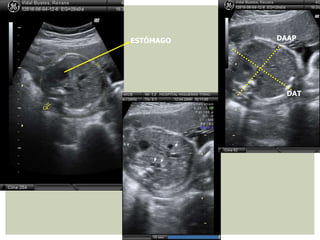

ABDOMEN

DAAP DAT CA

¿ QUÉ MEDIR ?

CC LF

+ EPF

CA = (DAAP + DAT) x 1,57

DAAP

DAT

ESTÓMAGO

EVALUACIÓN ANATOMÍA FETAL ABDOMEN Evaluarpared abdominal ant y tracto GI. No muy útil para EG, SÍ PARA EPF ¿ DÓNDE MEDIR ? PLANO TRANSVERSO A ALTURA DE CÁMARA GÁSTRICA Y VENA UMBILICAL, DE PIEL A PIEL

• 66.

EVALUACIÓN ANATOMÍA FETAL ABDOMEN DAAPDAT CA ¿ QUÉ MEDIR ? CC LF + EPF CA = (DAAP + DAT) x 1,57